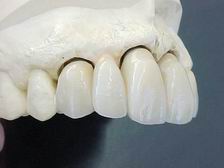

Prótese metalocerâmica personalizada